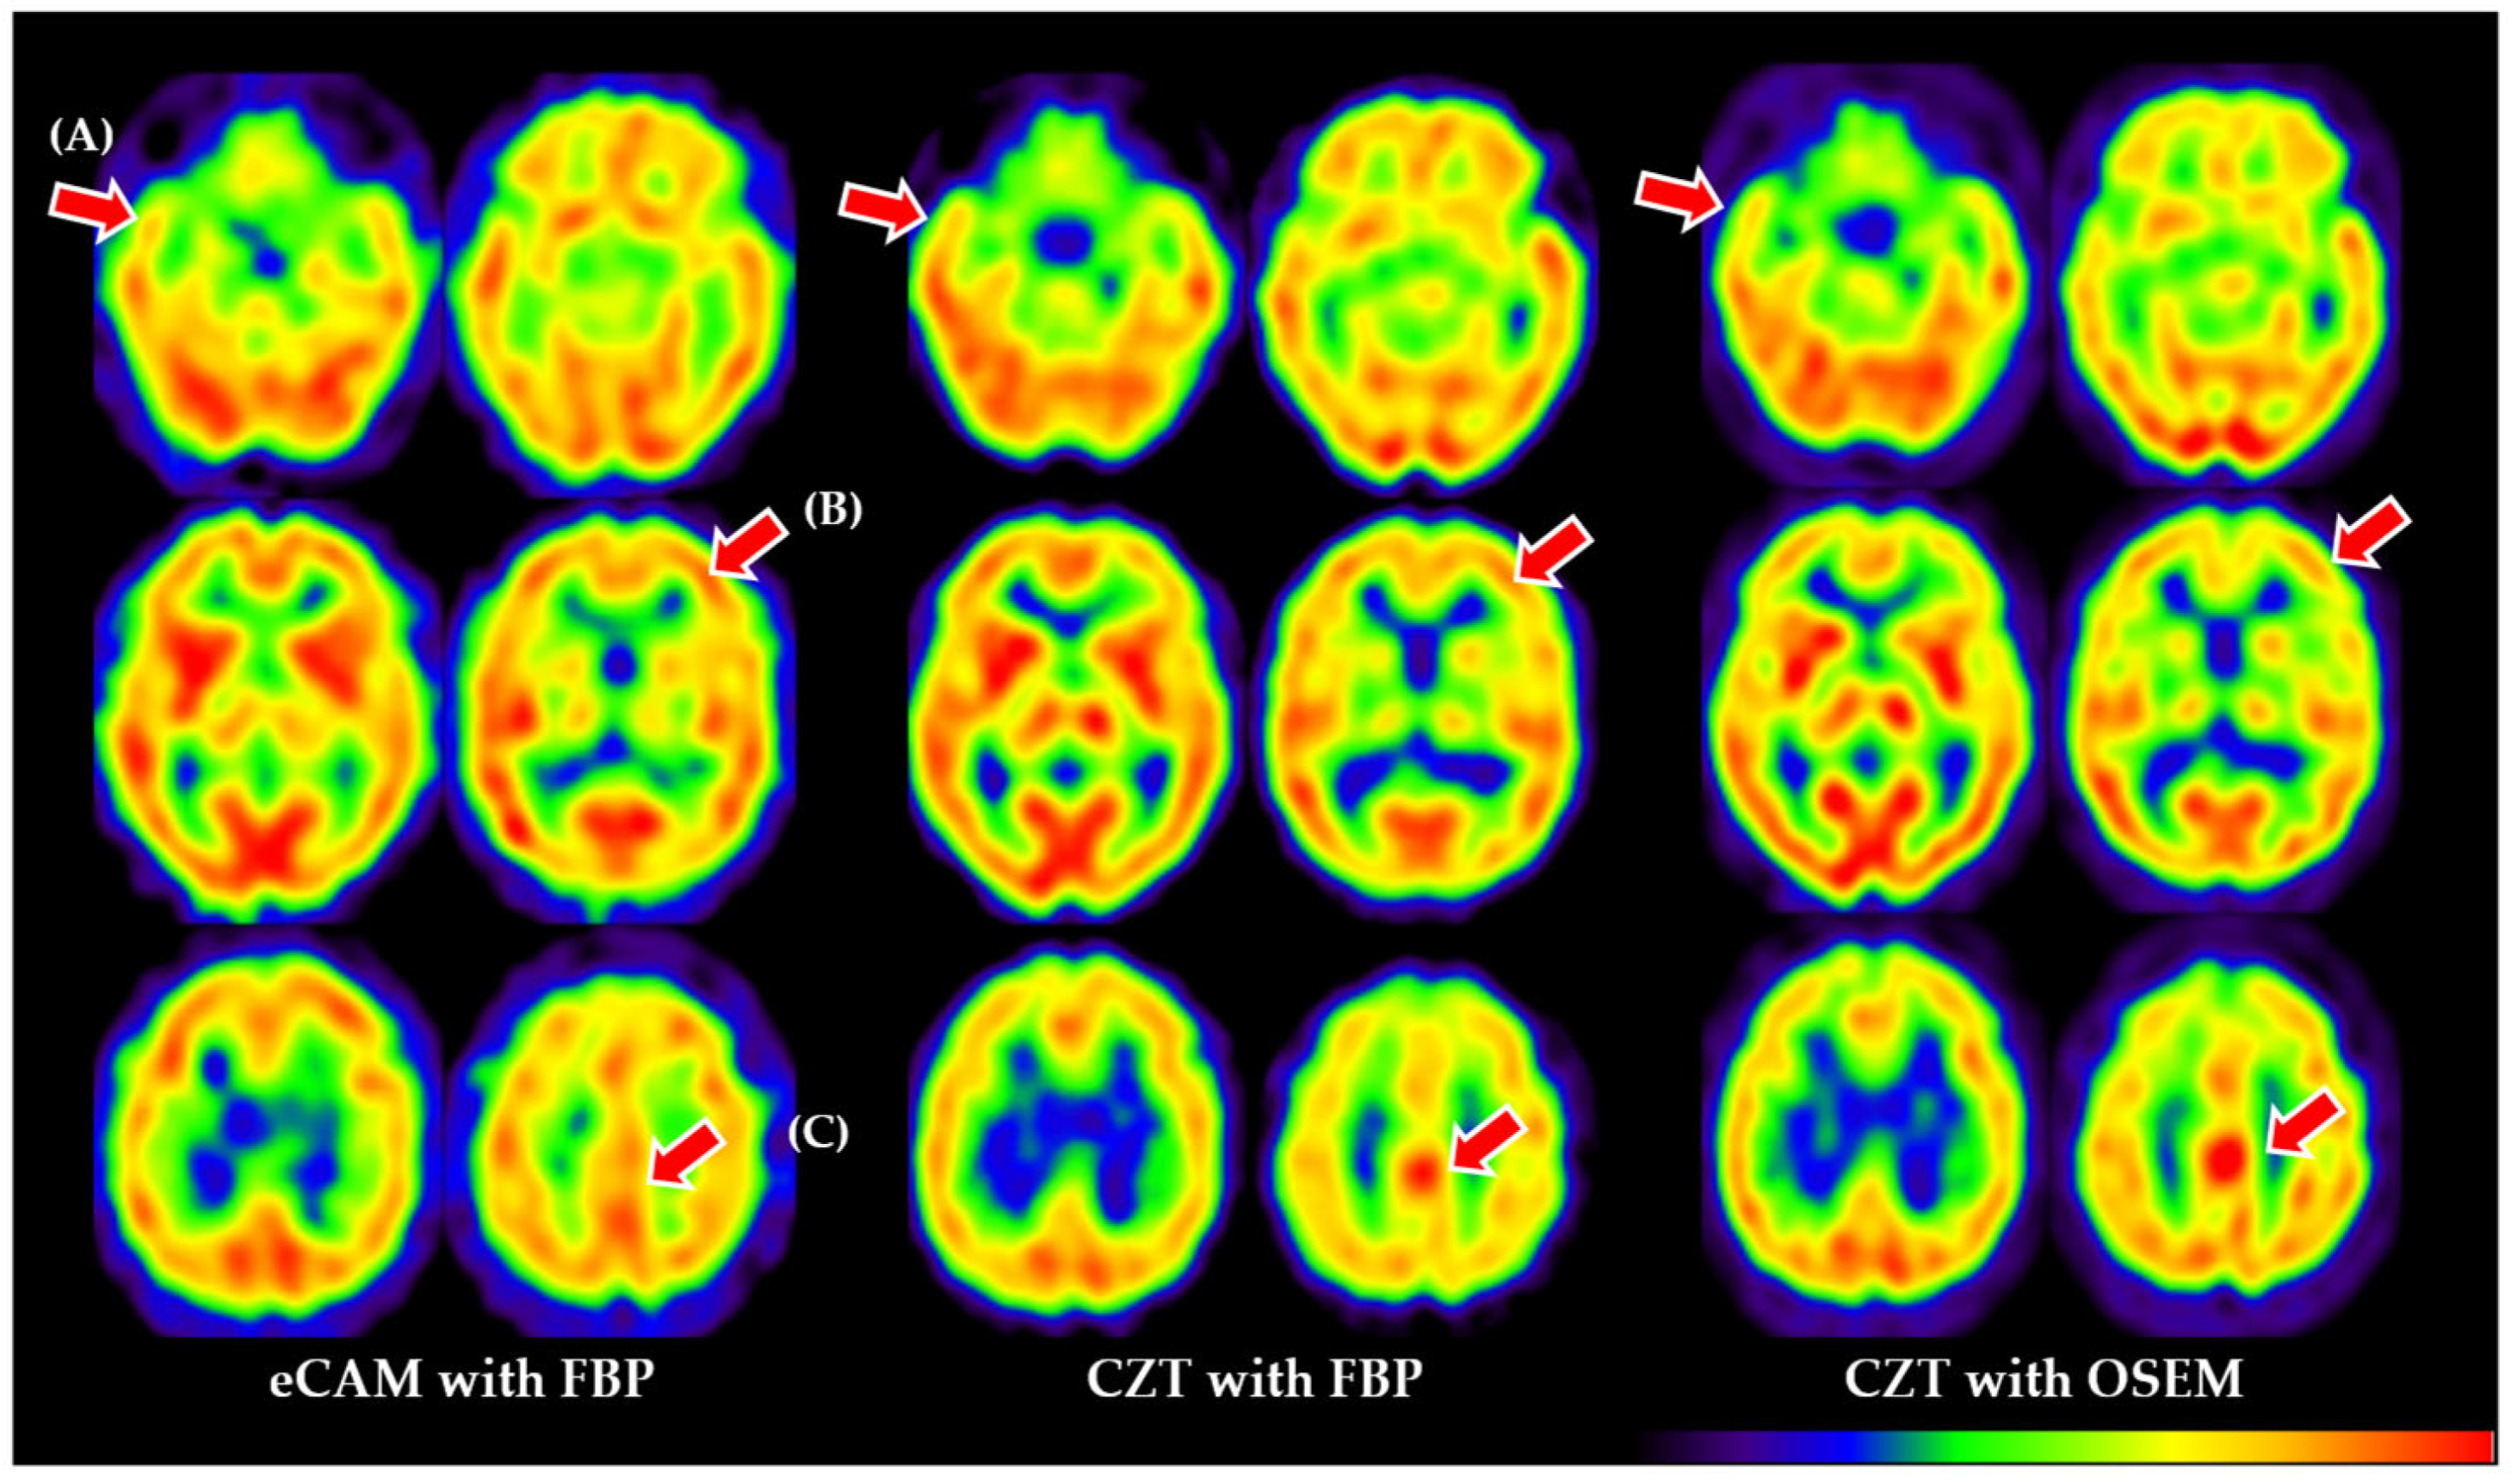

Recent advances, especially in solid-state cadmium–zinc–telluride (CZT) cameras and pinhole collimators, have allowed for resolutions of up to 3-6 mm [2] plus higher white/gray matter contrast [3]. This should translate to increases in diagnostic accuracy, similar to trends reported in other fields [4,5], but head-to-head comparisons of CZT SPECT vs. SPECT/CT (using filtered back projection [FBP] or ordered-subset expectation maximization [OSEM]) with regard to neurodegenerative diseases are currently scarce (Figure 1). Also of concern is the training regimen required to adapt to CZT; low availability and higher costs to train may result in readers being unfamiliar with the higher resolution and contrast.

The contrast was 1.615 ± 0.096 for CZT and 1.458 ± 0.068 for eCAM, with CZT being significantly higher (p < 0.001, Cohen’s d = 0.38). Figure 1 summarizes the differences among all utilized imaging methods (eCAM with FBP, CZT with FBP, and CZT with OSEM). When comparing diagnostic performance metrics between eCAM and CZT SPECT, both readers demonstrated similar patterns (Table 2). For the psychiatrist, sensitivity decreased from 75.0% (6/8) with eCAM to 62.5% (5/8) with CZT, while specificity improved slightly from 66.7% (14/21) to 71.4% (15/21). Overall accuracy remained unchanged at 69.0% (20/29). For the radiologist, sensitivity was maintained at 87.5% (7/8) for both modalities, but specificity decreased from 57.1% (12/21) with eCAM to 42.9% (9/21) with CZT, resulting in a reduction in overall accuracy from 65.5% (19/29) to 55.2% (16/29). Due to the small sample size, formal statistical comparison using McNemar’s test could not be reliably performed.

The most commonly reported SPECT systems, such as our eCAM system, are Anger-type systems based on the use of NaI (sodium iodide) as the scintillator with an adjacent vacuum tube called a photomultiplier tube. The cylindrical shape of the vacuum tube creates a significant limitation as it cannot cover the entire area of the scintillator, resulting in signal loss and irreversible degradation of image quality. A SPECT system using cadmium–zinc–telluride (CZT) as a scintillator and photomultiplier has recently become commercially available. CZT exploits the ability of a semiconductor to convert incident radiation into an electrical signal at room temperature within the semiconductor, removing the need for a vacuum tube and reducing signal loss [14]. Additionally, radiation is detected by a charged screen with smaller holes than standard pixels, in which 5 eV is sufficient to generate an electron–hole pairing; this results in higher resolution, contrast, and sensitivity [14] (Figure 1). Initially, CZT devices were developed and dedicated to cardiac use, but a whole-body device has recently become commercially available and was installed at our hospital in 2018. However, due to high cost, CZT systems have not seen widespread use, either domestically or internationally, and few studies report using this device. To the best of our knowledge, only reports on the cardiac sympathetic nerve [15], brain dopamine receptors [16], and bone scintigraphy [17] have been published using CZT detector technology.

Figure 1. Representative brain scans showing key differences between eCAM with FBP (left), CZT with FBP (center), and CZT with OSEM (right). Red arrows indicate (A) improved temporal lobe definition in CZT images; (B) enhanced gray/white matter contrast, with sharper boundaries visible in CZT images; (C) different visualization of the posterior cingulate gyrus, a critical region for Alzheimer’s disease diagnosis. Note the progressively improved image clarity from left to right, with CZT OSEM reconstruction providing the highest definition of anatomical structures. eCAM = Brand name for single-photon emission computed tomography camera; FBP = Filtered back projection; CZT = Cadmium–zinc–telluride; OSEM = Ordered-subset expectation maximization.